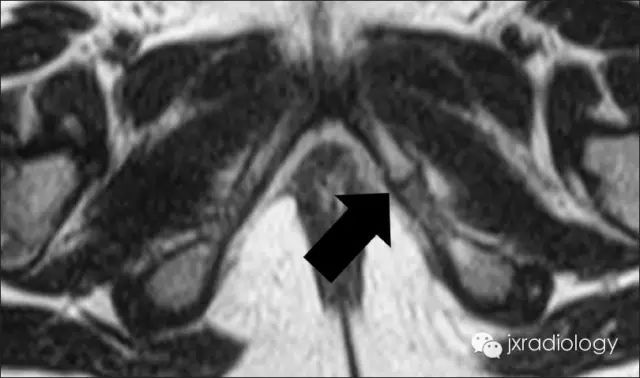

MRI:MRI对软组织及其病变范围能很好的显示。

信号改变(T2W多为高信号,T1WI多为低信号,脂肪抑制序列多为高信号)以及骨质与周围软组织的对比度增强三大征象,可能是局部机械应力的结果,但缺乏特异性,并进一步提出坐骨耻骨之间的“纤维连接”可能是坐骨耻骨软骨炎的MRI特有征象。